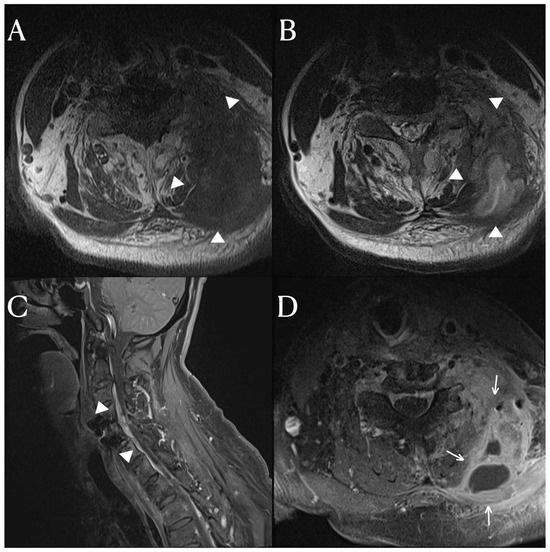

A 65-year-old patient presented a fever that began three weeks prior. He had a complete spinal cord injury below the C4 level 20 years ago in an accident and underwent anterior cervical discectomy and fusion (ACDF) on C4-5 due to a fracture and dislocation of the cervical 4–5 vertebrae. This patient was diagnosed with a urinary tract infection at another hospital and treated with antibiotics. Urinary tract infections are commonly seen in patients with neurogenic bladders in spinal cord injury. Despite treatment, the fever persisted. The patient was referred to our hospital for further evaluation and treatment due to the persistent fever. Upon examination at our hospital, there was a mass-like lesion in the posterior neck. The inflammatory markers were still elevated. We performed cervical spine MRI scans, which revealed an anterior epidural space abscess and inter-intramuscular abscess involving the left posterior neck area, extending from C3 to C6 (Figure 1). In addition to the soft tissue infection, there was also osteomyelitis in the lamina and transverse processes of the cervical spine, for which vancomycin and a taxolactam (piperacillin sodium and tazobactam) were administered. To address the abscess, a 10 cm incision was made in the left posterior cervical area, allowing for massive irrigation and abscess removal, followed by a curettage of the cervical posterior bony arch. After the abscess removal and bony curettage, primary closure was performed. The duration of antibiotic treatment was anticipated to be between 4 and 8 weeks, depending on the clinical symptoms and the results of the inflammatory markers.

Figure 1. The cervical spinal MRI images, T1 (A) and T2 (B) weighted axial scans revealed an inter-intramuscular abscess (arrowhead) involving the left scalene, multifidus, semispinalis cervicis, and semispinalis capitis muscles, as well as the levator scapulae. The T1-weighted enhanced axial scan (D) displayed a rim-enhanced fluid collection (arrow) indicative of an abscess. The T1-weighted sagittal scan (C) demonstrated an epidural abscess (arrowhead) extending from the C3 to C6 levels.